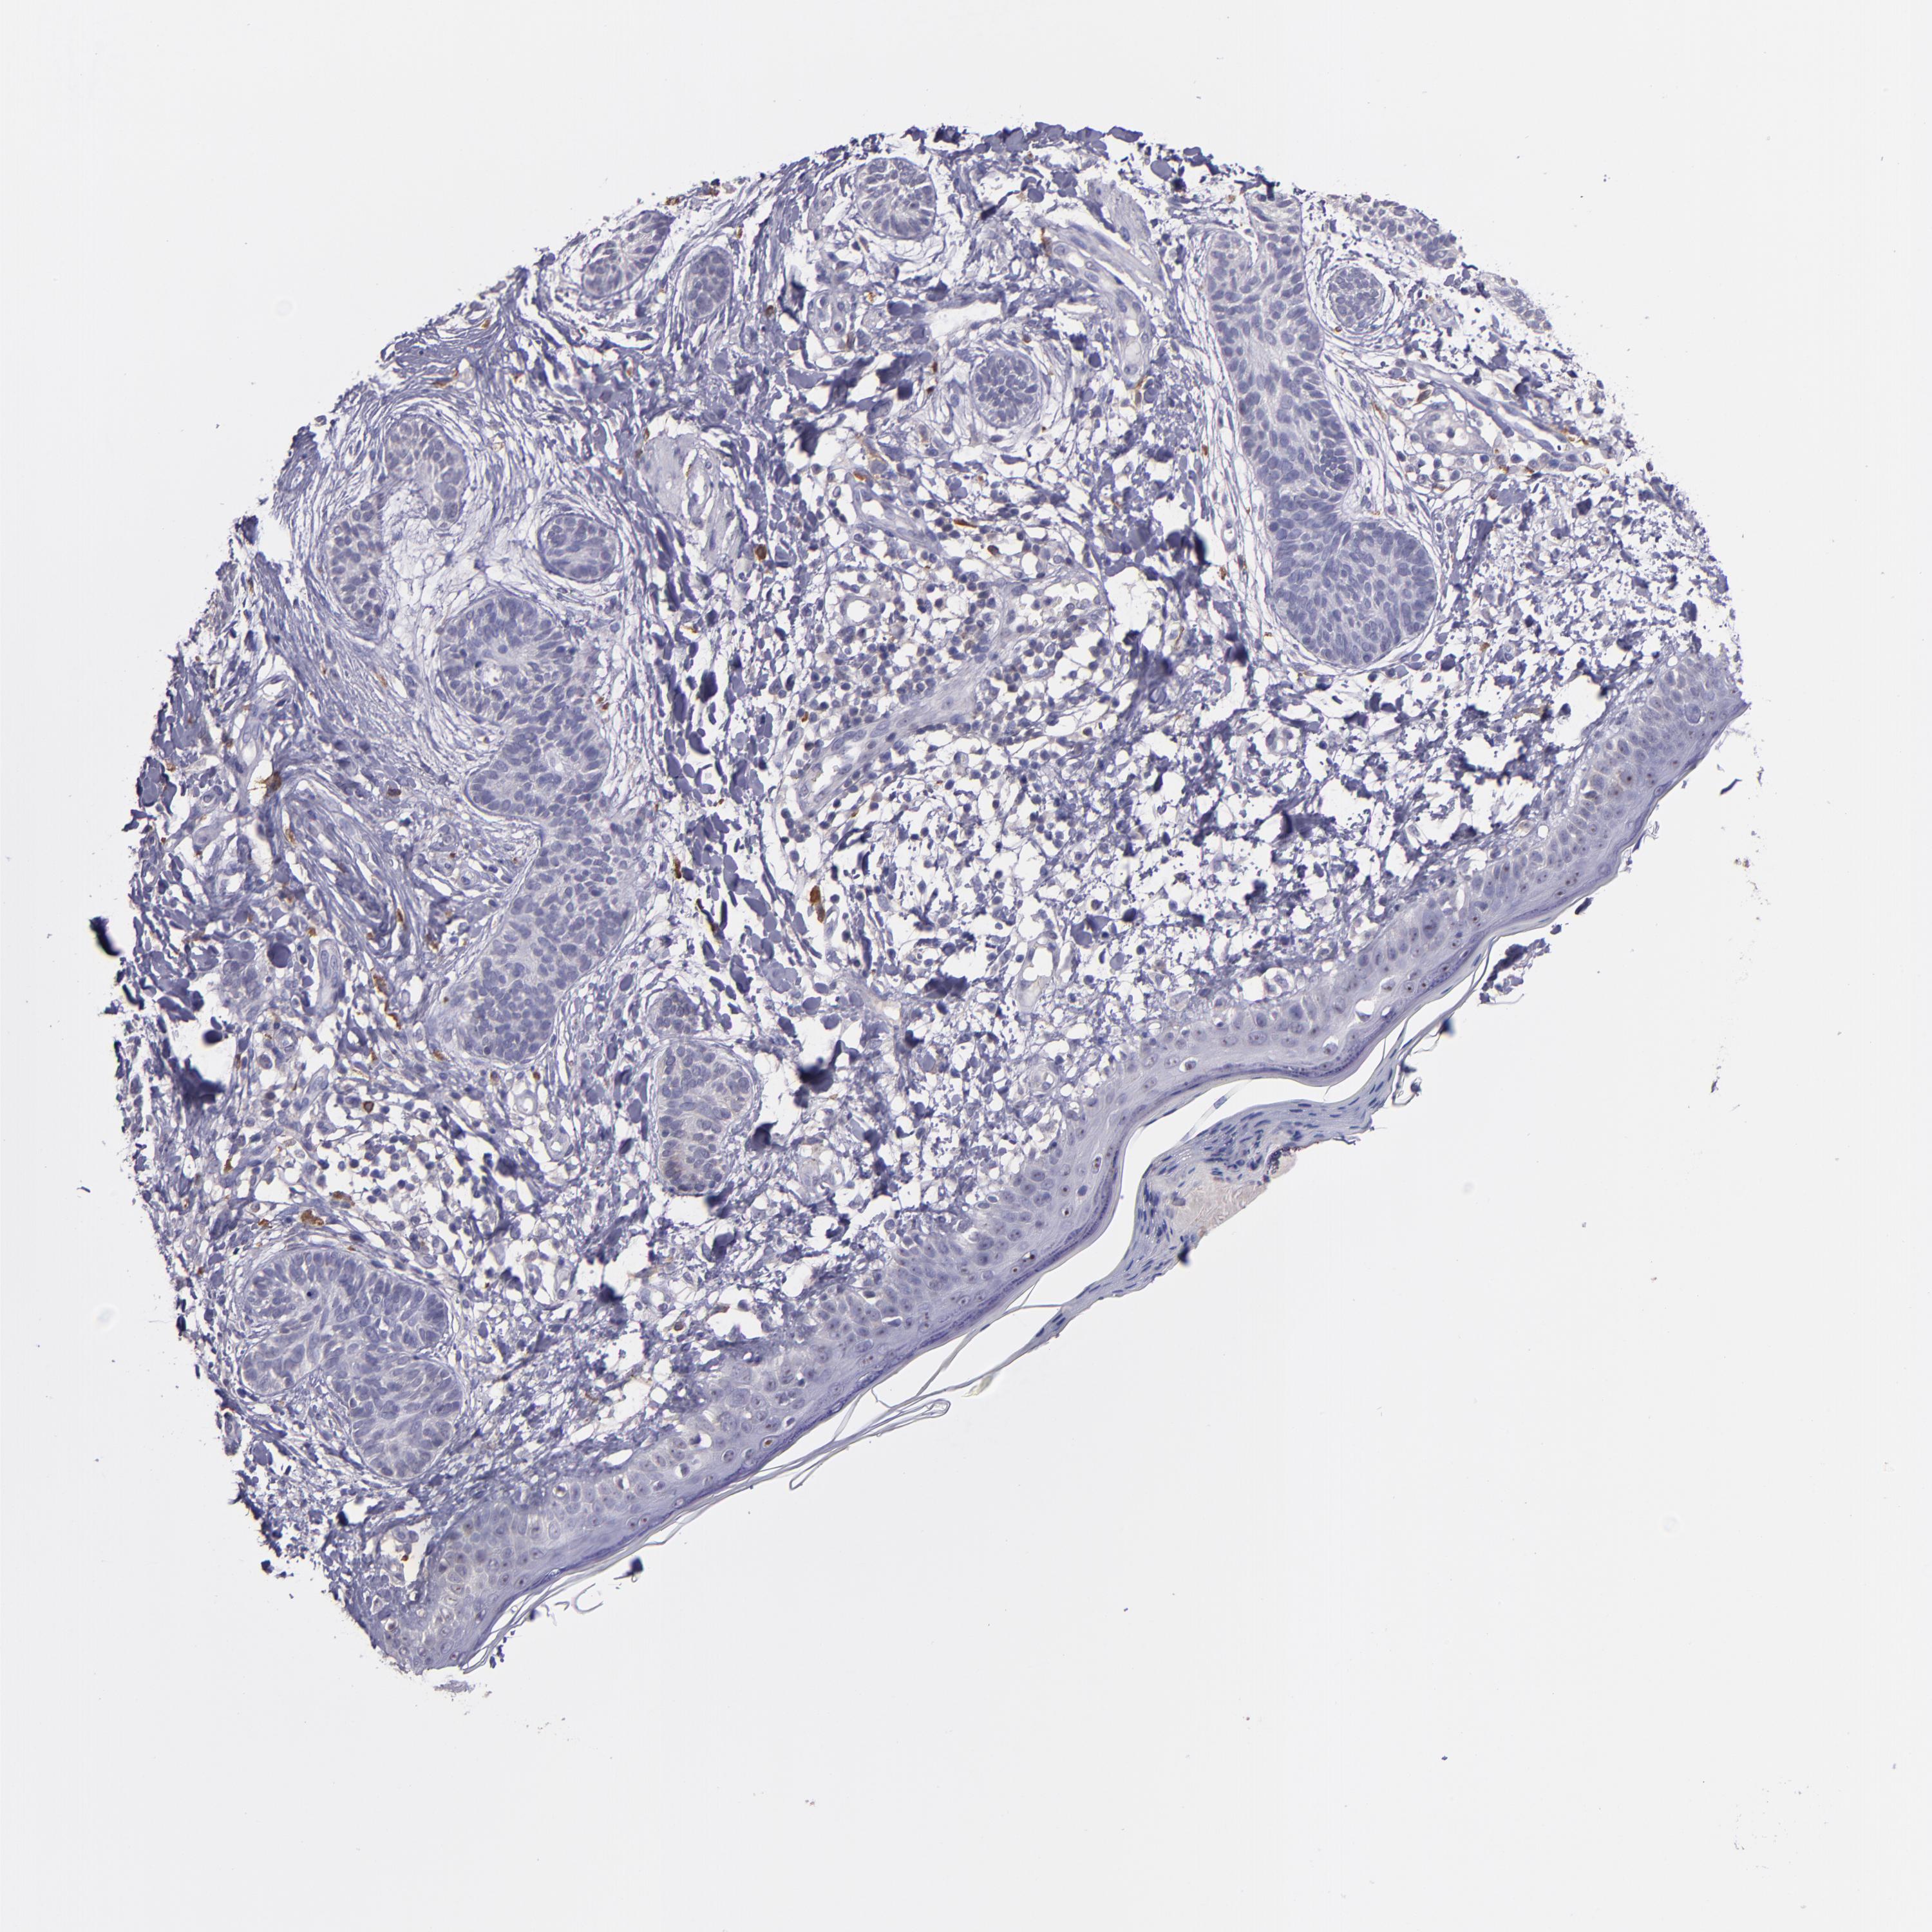

SKIN CANCER - Protein expressioni

A mouse-over function shows sample information and annotation data. Click on an image to view it in a full screen mode. Samples can be filtered based on level of antibody staining by selecting one or several of the following categories: high, medium, low and not detected. The assay and annotation is described here.

Antibody stainingi

Antibody staining in the annotated cell types in the current human tissue is reported as not detected, low, medium, or high, based on conventional immunohistochemistry profiling in selected tissues. This score is based on the combination of the staining intensity and fraction of stained cells.

Each image is clickable and will lead to virtual microscopy that enables deeper exploration of all samples and also displays staining intensity scores, fraction scores and subcellular localization as well as patient and tissue information for each sample.

Antibody HPA001667

Antibody CAB016724

Squamous cell carcinoma, NOS

Basal cell carcinoma

Squamous cell carcinoma, metastatic, NOS